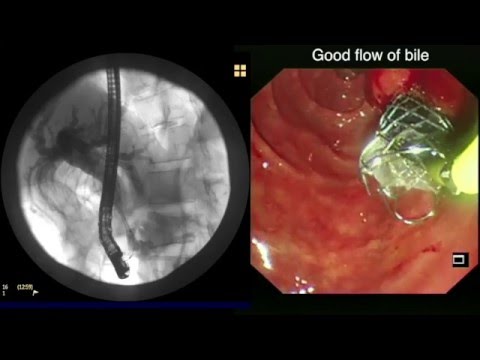

ERCP: Needle knife fistulotomy in a patient with pancreatic cancer